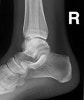

- 발목삔 후 X-ray를 찍고 나서 "뼈에는 이상이 없고 인대가 좀 늘어났어요."라는 말을 자주 듣게 됩니다.

발목 염좌 환자에게 X-ray를 찍는 것은 골절을 감별하기 위함입니다.

X-ray에서 인대는 볼 수 없습니다. 따라서 X-ray로 인대가 늘어났는지의 여부는 알 수 없습니다.

발목 인대의 상태를 영상으로 보기위해서는 X-ray가 아닌 MRI가 필요합니다.

발목 인대가 부분 파열되거나 완전 파열되어 발목에 불안정성이 있을 때에는 MRI를 촬영해 볼 수 있습니다.

하지만 경도의 발목 염좌라면 MRI까지 촬영해야 할 이유는 없습니다.

간단한 이학적 검진과 보존적 치료를 통해 충분히 치료가 가능합니다.